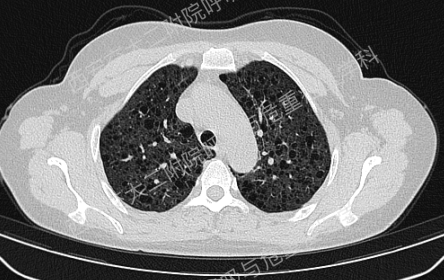

上图所示肺部多发囊性病变,双肺广泛分布,直径在2-10mm之间,壁薄,囊壁间组织相对正常。结合育龄期女性等临床资料,不难诊断淋巴管平滑肌瘤病(LAM)。对疑似LAM的女性的初步评估还应包括血管平滑肌脂肪瘤的筛查、淋巴管受累以及是否存在未被诊断的结节性硬化症。该例患者经评估后诊断散发型S-LAM。